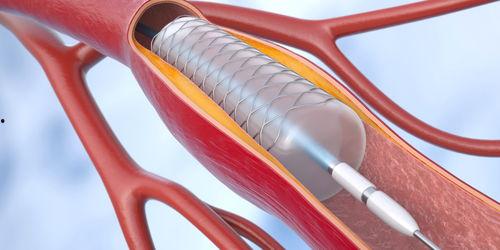

说起心脏支架,那可是心脏疾病患者的一大福音。心脏支架,顾名思义,就是用来支撑心脏血管的一种医疗器械。在我国,心脏支架的研发和生产一直备受关注。近年来,我国在心脏支架领域取得了显著的成果,成功研发出具有自主知识产权的国产心脏支架。

国产心脏支架在技术方面也毫不逊色。我国科研团队经过多年的努力,成功研发出具有自主知识产权的支架材料,并在支架设计、制造等方面取得了突破。这些技术优势,使得国产心脏支架在临床应用中表现出色。